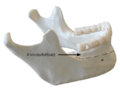

On the maxillae, the alveolar process is a ridge on the inferior surface, and on the mandible it is a ridge on the superior surface. It makes up the thickest part of the maxillae.